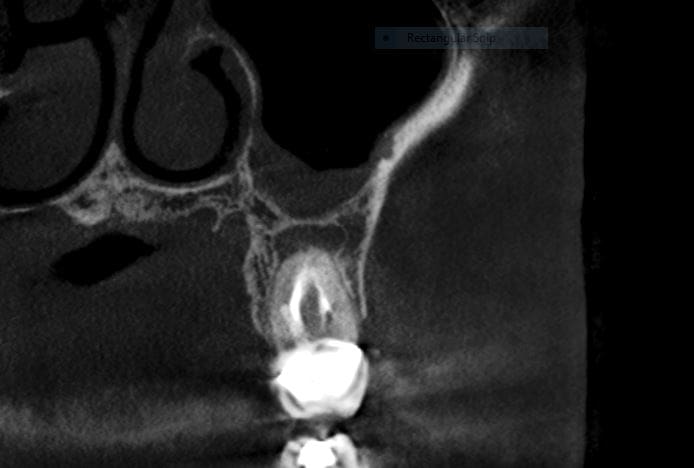

- Insufficient technology, which is unable to detect current infections before a root canal procedure.

- Undetected accessory canals housing harmful bacteria.

- Microtubules in the root housing harmful bacteria.

An annual wellness assessment at Origin Dental Wellness coupled with our 3D Cone Beam Scan once a year is the most proactive and least expensive way someone can prevent future illness, expensive surgeries, and life of wasted “quick fixes” that always fall short.